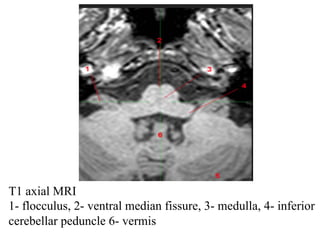

T1 axial MRI

1- flocculus, 2- ventral median fissure, 3- medulla, 4- inferior

cerebellar peduncle 6- vermis